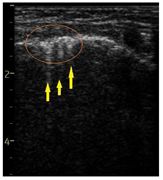

| LUS Score | 0 Points | 1 Point | 2 Points | 3 Points |

| Image | ![]() | ![]() | ![]() | ![]() |

| Description of image | Normal or physiological pattern displaying A-lines (right part), along with two sparse B-lines (yellow arrows) per intercostal space | Three sparse B-lines (yellow arrows) per intercostal space, accompanied by pleural abnormalities, such as irregularities or thickening (orange circle) | Small peripheral consolidations smaller than 1 cm (red dotted area), a small area with ‘white-lung’ appearance, adjacent coalescent or merging B-lines | Substantial peripheral consolidations (marked with red) wider than 1 cm with the presence of air bronchograms (hyperechoic areas inside); the image is from an infant with bacterial pneumonia not included in this study |